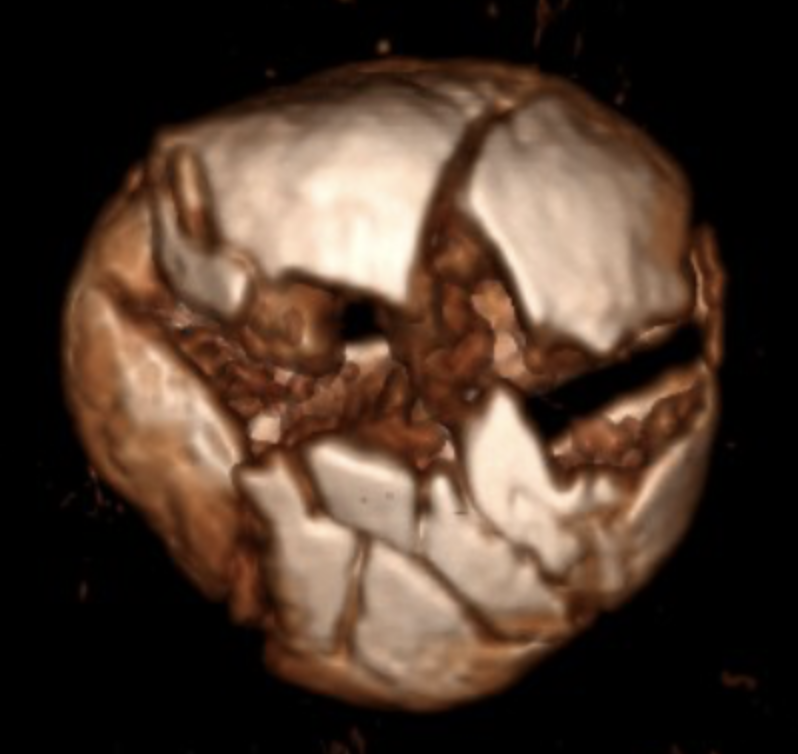

This narrative recounts my fourth knee surgery, the third at HSS. A decade ago, I sought care at HSS following a tibial plateau fracture operated on in the Alps. Dr. Helfet oversaw my recovery and later performed hardware removal on my severely osteoporotic bone. Unfortunately, eight years later, I broke the same knee again in the Alps. Without hesitation, I flew back to New York, confident beyond any doubt that HSS would provide unparalleled orthopedic care.

In an incredible three-hour surgery, Dr. Helfet reconstructed my shattered knee cap into no fewer than 20 pieces. Eleven months later, after a flawless recovery, Dr. Helfet and I decided to remove the 10 screws and plate. Once again, he successfully navigated surgery on my genetically fragile bone.